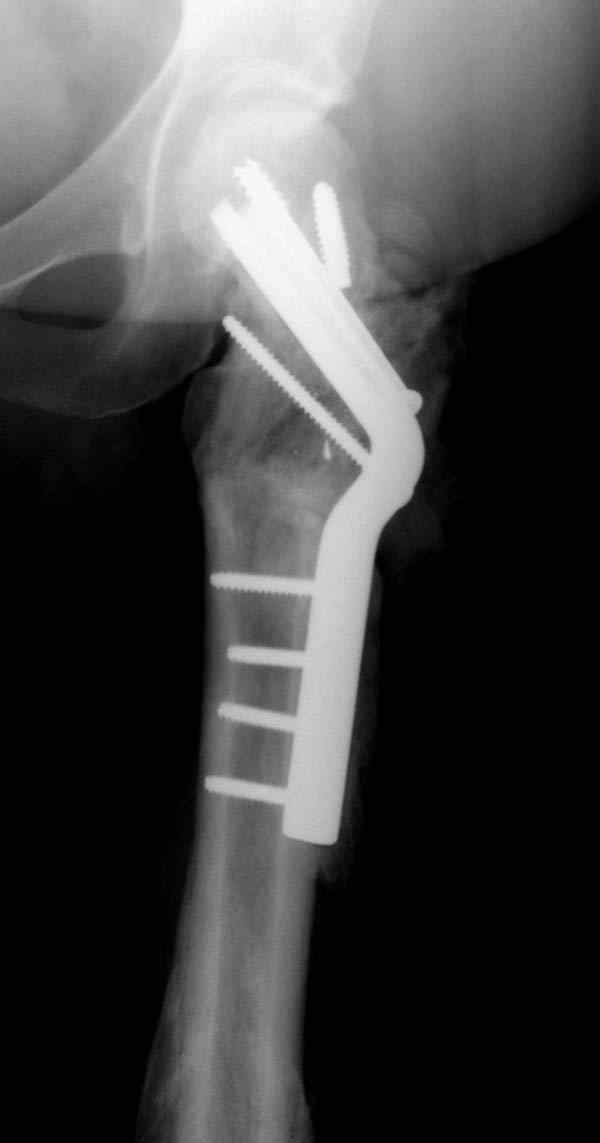

Учитывая молодой возраст больного, из всех рекомендуемых вариантов для лечения ложного сустава шейки предпочтительным является вальгусная остеотомия (на сайте имеются прежние разборы) из-за простоты исполнения и биомехнических преимуществ.

А открытая репозиция шейки окончательно не лишит кровоснабжения головку? Не говоря о технической сложности вальгизации проксимального отдела бедра при фиксации гвоздем.

Наверно, вариант с вальгизирующей остеотомией с фиксацией blade plate или DHS более щадящий. А диафиз можно рефиксировать ретроградно. Или про эндопротезирование с очень длинной ножкой подумать.

Несмотря на пессимистические прогнозы, у молодых

коррегирующая вальгусная остеотомия является более

приемлемым.

Представленные случаи доказательства тому, что еще

имеется резервы на восстановление даже у 5-6 месячных ложных суставов шейки.